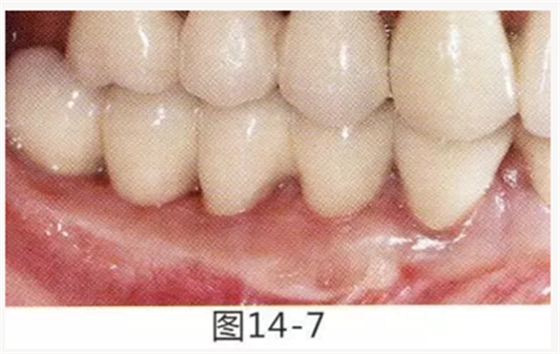

圖14-7 配戴最終修復(fù)體完成5年后的狀態(tài)。保持良好。